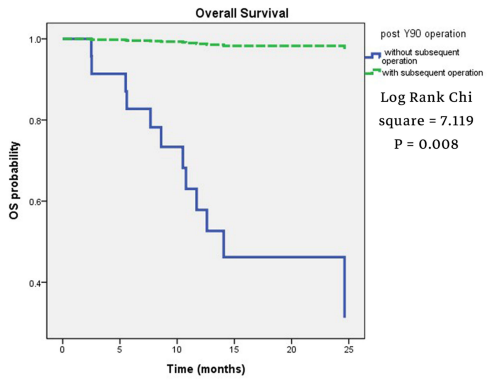

张宇华表示,门诊中首诊的肝癌患者只有20-30%有手术机会,剩余百分之七八十的首诊患者因为发现时已经是中晚期,很多已经没有了手术机会,而手术切除是肝癌患者目前唯一可能获得长期生存的治疗选择。

“还有一部分肝癌患者是由脂肪肝发展而来的。” 张华宇说,长久以来,人们都以为肝癌很难治愈,尤其是中晚期,一旦被确诊,感觉是被判了死刑,“实际上,现在对于肝癌的治疗发展很快,有很多手段,除了手术之后,对那些初诊不能手术的患者,还可以采用转化治疗,包括介入治疗,靶向免疫治疗等等,也就是先“保守”治疗,将肿瘤缩小,再寻求手术切除的机会。”

以ALPPS为例,这也是一种有效的治疗手段,让患者可以不用进行肝移植就能得到手术切除,毕竟,肝源难寻。

“传统的二步肝手术创伤大,并发症多,很多病人因此止步于第一步。腹腔镜技术应用于ALPPS,两步手术都通过微创来完成,明显减少了患者的创伤,在第一步手术中,胆漏、出血等并发症发生率特别低,从而保证了第二阶段手术的顺利进行。”